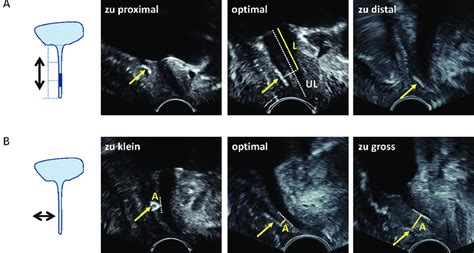

Die Prävention von Komplikationen beginnt bereits bei der Operationsplanung. Die Pelvic-Floor-Sonografie ist essenziell für die Diagnose von Früh- und Spätkomplikationen und zur Bestimmung der Urethralänge und -mobilität. Die fundierte Ausbildung des Operateurs ist der wichtigste Faktor zur Prävention und Erkennung von Komplikationen. Um die Komplikationsrate niedrig zu halten, sind jährlich über 40 Operationen pro Schlingentyp durch denselben Operateur erforderlich.

Blasenperforationen gehören zu den häufigsten intraoperativen Komplikationen, sind aber bei sofortiger Erkennung einfach zu korrigieren. Auch Urethra-, Vagina- oder Darmperforationen können auftreten; Darmverletzungen sind selten, aber gravierend. Blasenentleerungsstörungen, ebenfalls relativ häufig, können intraoperativ durch Anpassung des Bandes reduziert werden. Unmittelbar postoperativ können Ursachen für Entleerungsstörungen mittels Pelvic-Floor-Sonografie identifiziert werden. In den ersten Tagen nach der Operation können zu dicht liegende Bänder durch erneute vaginale Nahtöffnung einfach gelockert werden. Eine Bandlockerung ist meist nicht notwendig, wenn der Band-Urethra-Abstand über 3 mm liegt, da sich Blasenentleerungsstörungen nach Abschwellen der Ödeme von alleine zurückbilden.

Bis etwa eine Woche nach der TVT-Insertion können Komplikationen relativ einfach und mit gutem Ergebnis korrigiert werden. Eine wichtige Rolle spielen dabei die Kontrollen am 1.-3. postoperativen Tag mit Restharnmessung, Hustentest, Zystoskopie und Bestimmung der Bandlage.